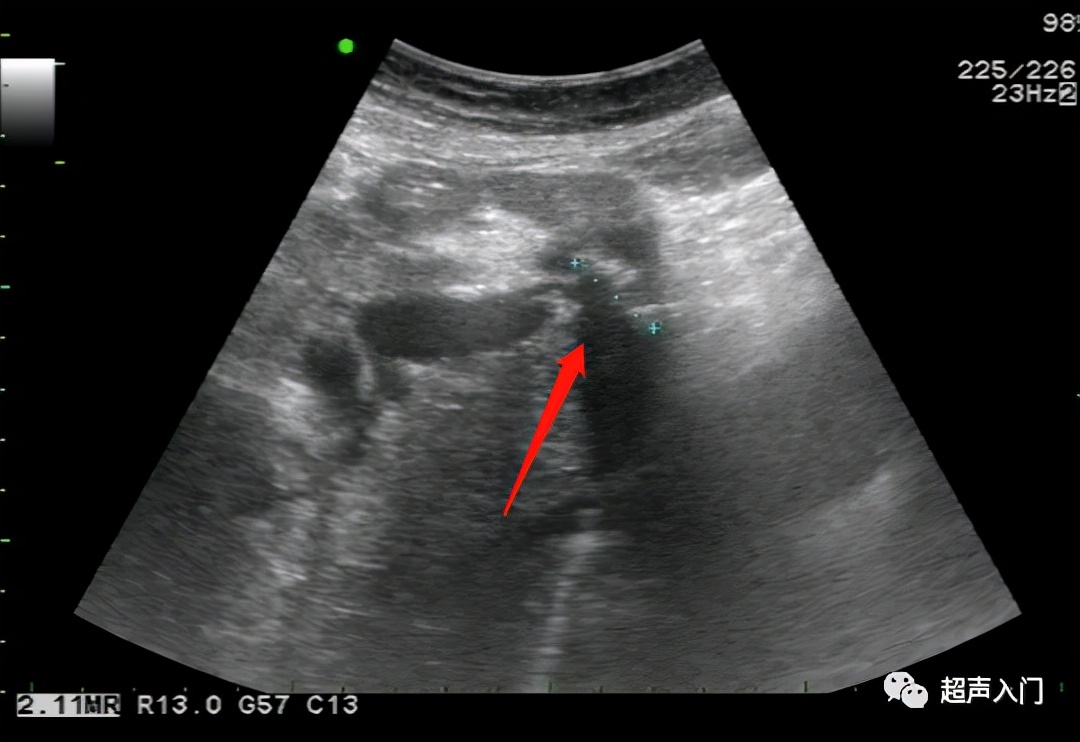

01 肝囊肿

(肝里面那个黑洞洞)